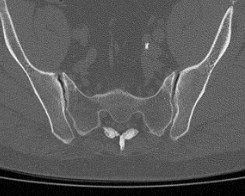

- сужение суставной щели (в норме она составляет 4-5 мм);

- на начальных стадиях заболевания возможно расширение суставной щели;

- на поздних стадиях патологии суставная щель полностью исчезает (полный анкилоз) или на КТ определяются «мостики» из соединительной ткани между суставными поверхностями (частичный анкилоз);

- уплотнение субхондральной (подхрящевой) кости, которое обычно сильнее выражено со стороны подвздошной кости, чем крестца;

- появление кист в субхондральной кости;

- эрозии на суставных поверхностях.